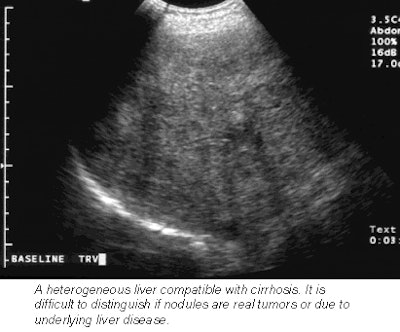

In order to test the clinical effectiveness of this phenomenon, researchers developed a multinational, four-center study in which 52 patients with known focal liver lesions were first imaged with unenhanced ultrasound.

![]() |

Next, each patient received an injection of Sonazoid, which was immediately followed by a pulse-inversion harmonic ultrasound scan that tracked the contrast in the bloodstream. A second scan 15 minutes later detects the contrast as it accumulates in liver cells. The contrast-enhanced scans boasted a 76% improvement in lesion conspicuity, a sensitivity improvement from 73% to 89%, and a jump in the number of confirmed metastases from 68 to 83.